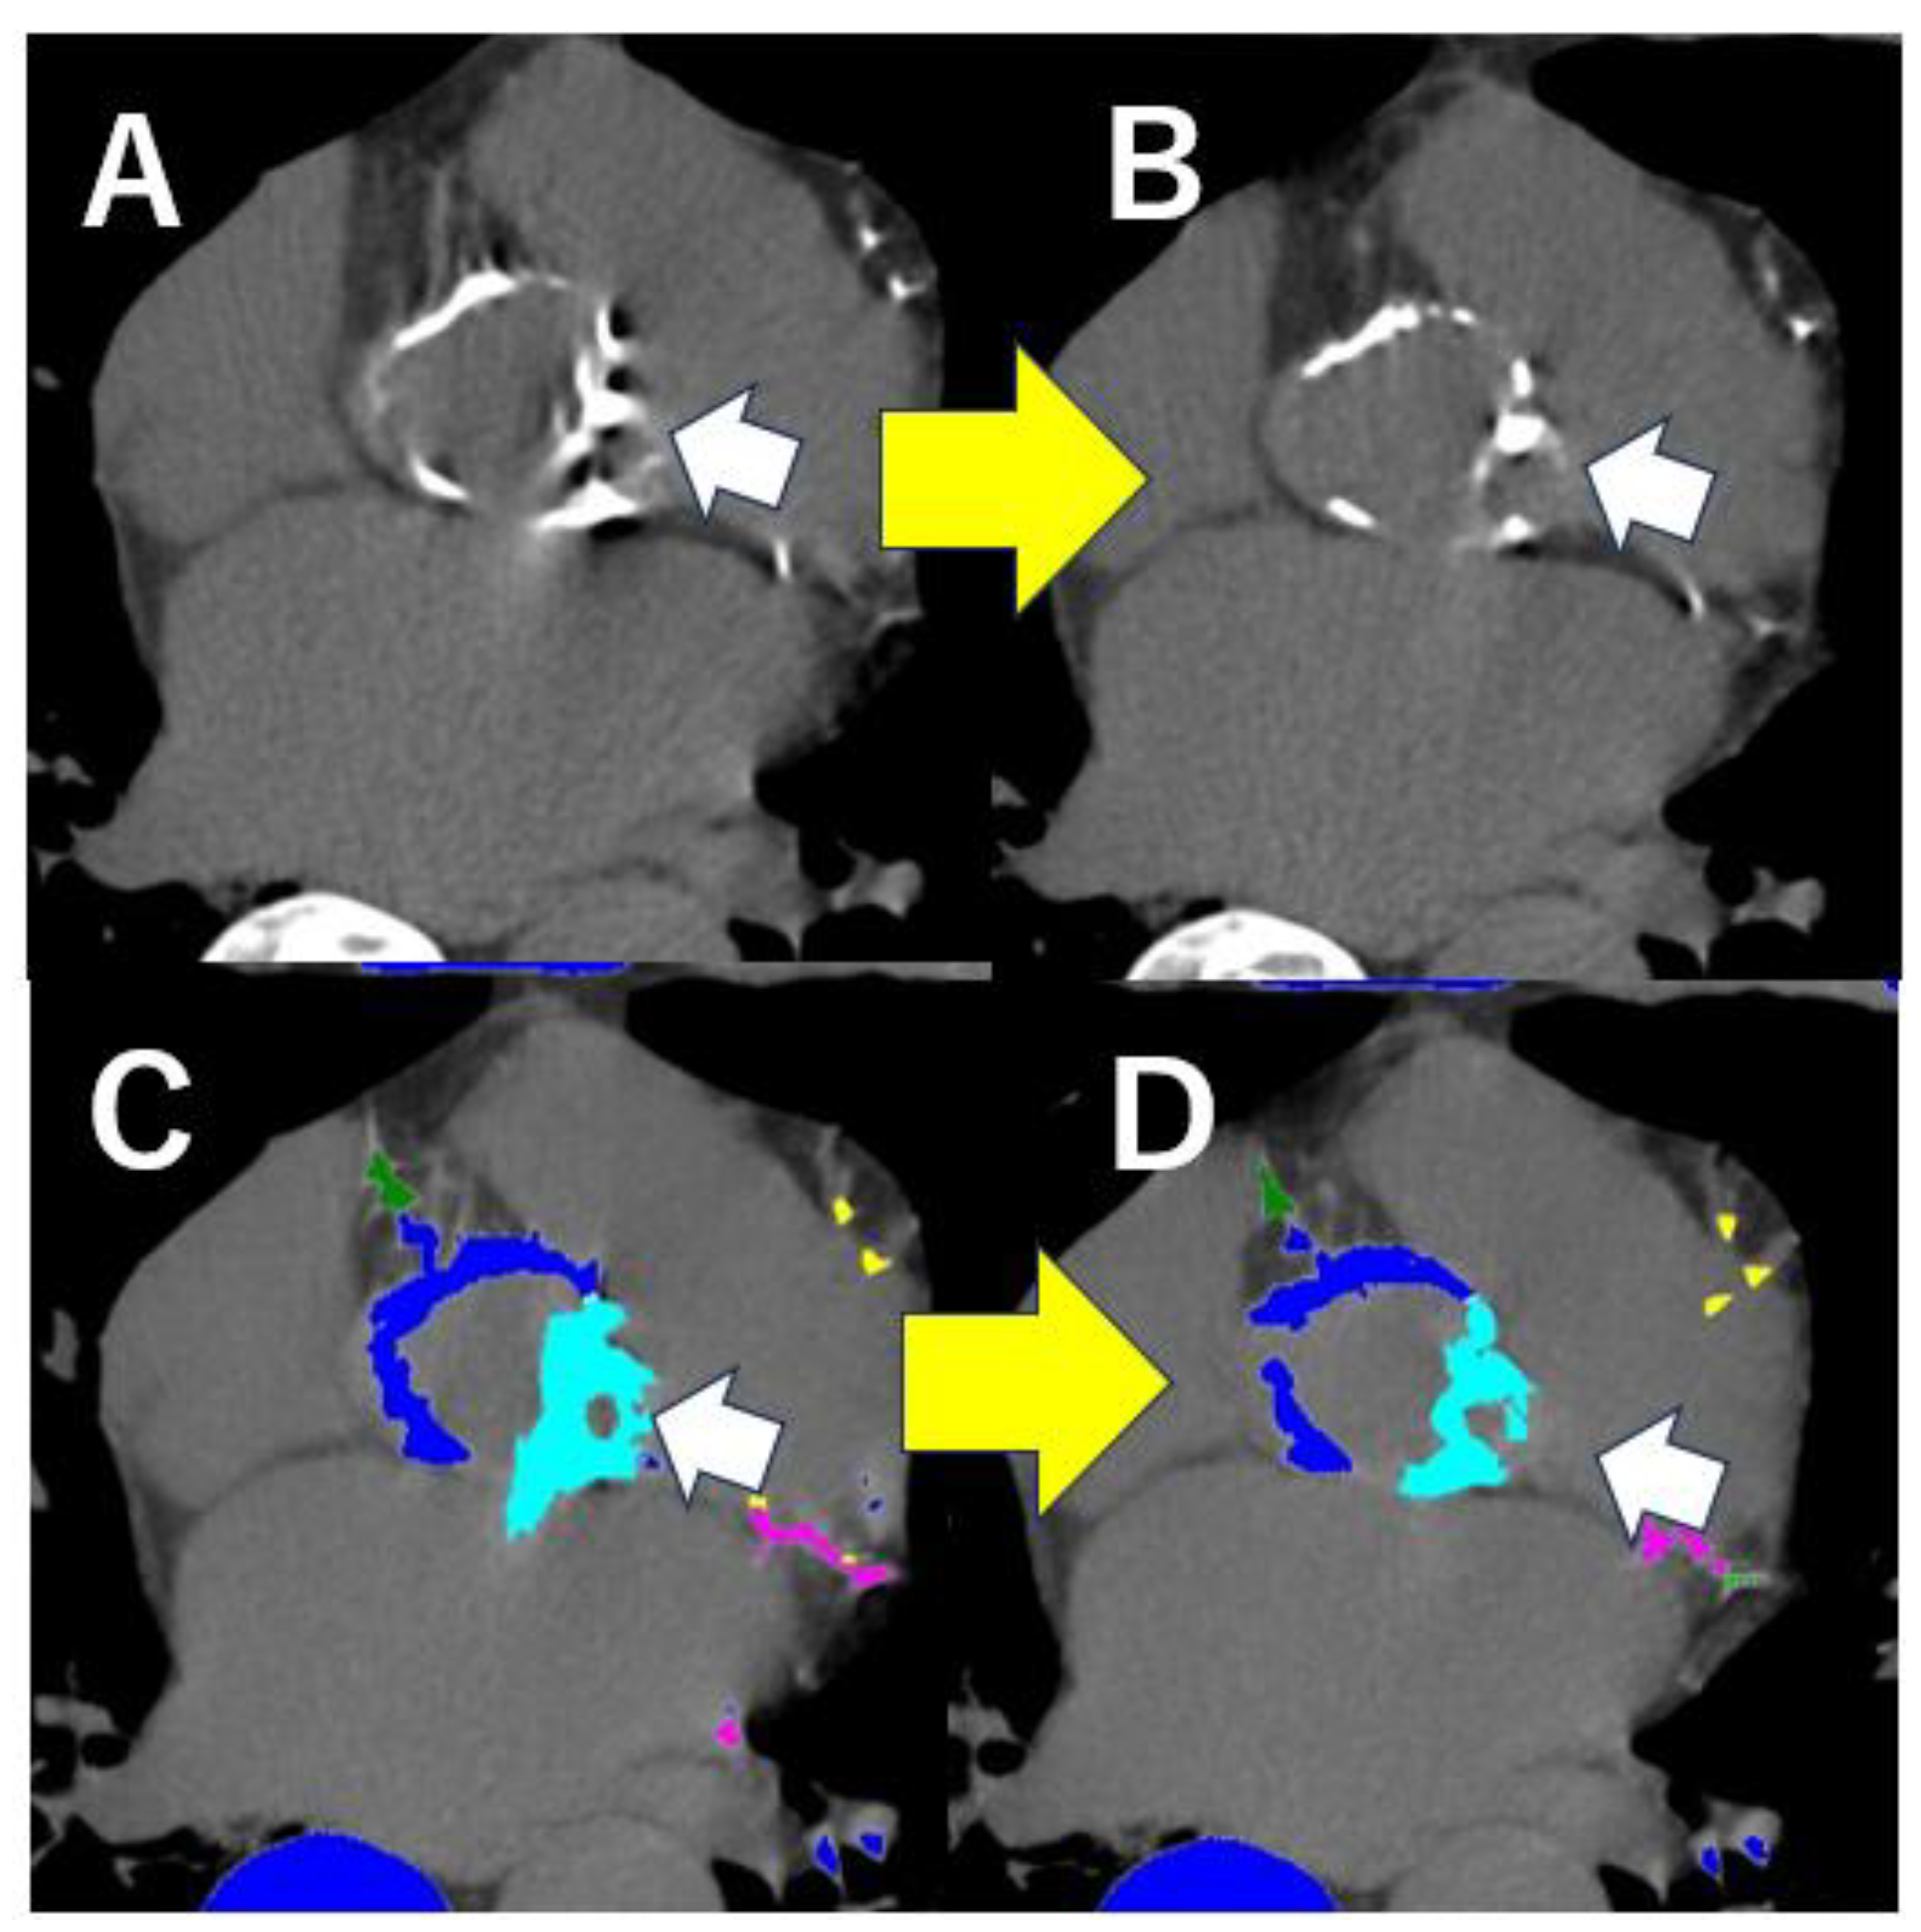

4.6. CT Analysis After TAVI